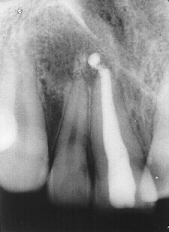

¿Te hicieron una endodoncia y no te tomaron ninguna radiografía? ¿Ni antes, ni durante, ni después del tratamiento? ¿No te enseño en una radiografía los 3 conductos (entradas) que te dijo que tenias? Mira, para realizar una endodoncia son FUNDAMENTALES los rayos POR ya que son la única manera de que el dentista y el paciente puedan ver que es lo que están haciendo, ya que sin ellos estamos literalmente a ciegas; por otro lado ¿hace cuánto te realizaron ese tratamiento? Muchas veces después de terminado el tratamiento la muelita o diente en cuestión queda un poco adolorido, sobretodfo al morder se siente un como "pellizco" pero que se tolera sin ningún problema, sobretodo si es apoyado con antiinflamatorios; ¿Qué debes hacer? Bueno, primero (y perdón por ser tan brusco en mi respuesta) acude con un endodoncista (no un dentista general, sino un especialista en endodoncia) si no conoces ninguno, acude con tu desntista, platícale lo que te pasa y preguntale "¿por que no me tomas una radiografía para ver que pasa?" si te contesta de forma negativa, pídele que te refiera con un especialista (o mínimo alguien que tenga rayos X) y explicale que tu investigaste y descubriste que una endodoncia se DEBE realizar con la ayuda de rayos X, hasta el momento no existe una manera de realizar un tratamiento como ese sin apoyo de la radiografía ya sea tradicional o digital(YA QUE COMO SE TRABAJA DENTRO DEL DIENTE NO HAY OTRA MANERA DE SABER DONDE DIABLOS ESTAMOS). Continua con los medicamentos por el tiempo que te indico y regresa a verlo, pero de ninguna mnaera dejes que comiencen a restaurarlo (ponerle la tapa) sin haber visto tu una radiografía, en ella debes ver tu diente y dentro de el unos "hilitos" de color blanco opaco que recorren la raíz en toda su longitud" sin salirse de esta (no es necesasrio ser dentista para ver en una radiografía donde empieza y termina la raíz de un diente). Por ultimo, cehca esta página, aquí veras como se ve en una radiografía un diente con endodoncia (el del lado derecho con la linea blanca enmnedio) y uno sin ella (el del lado izquierdo)

Pero sobretodo piensa que si quien te la realizo no te tomo ningún radiografía, entonces debes pensar en que lo que te hicieron no fue hecho de la mejor manera. Espero haberte respondido y aclarado tus dudas, si no, vuelve a preguntar, aquí estamos y que te mejores. Ah lo olvidaba, yo vivo en mexico y no se a que te refieres con "me duele la barra" ¿qué es la barra?